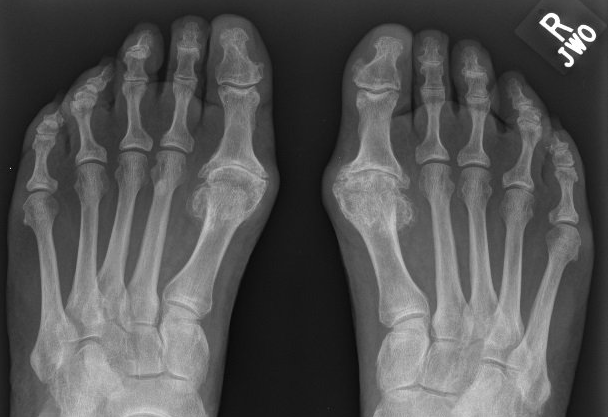

The 1st MTP joint is the most common

foot joint to become arthritic.

- Osteo-arthritis is common

- Other cause include rheumatoid arthritis, gout and severe hallux valgus ("bunion").

Like all arthritic joints, these big toe joints become stiff, painful and bulky.